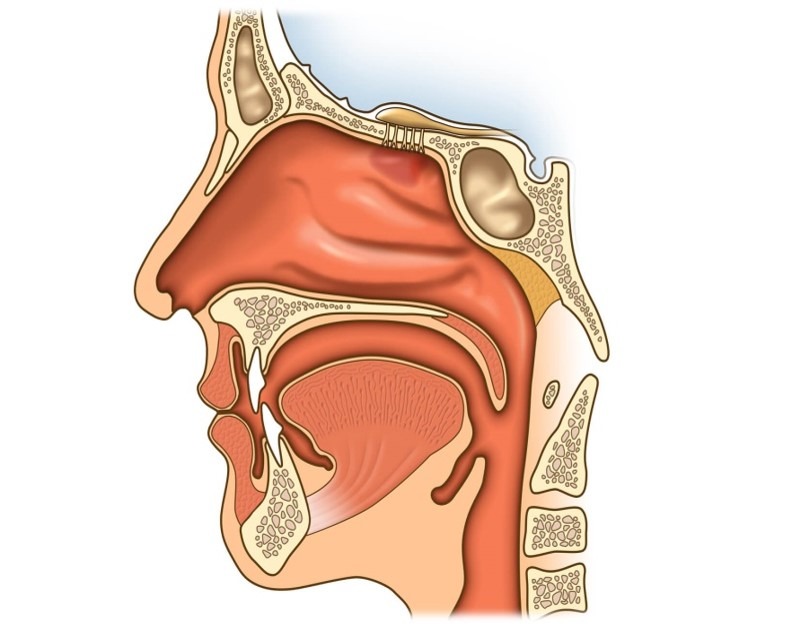

Строение носа и его пазух

Анатомическое строение носа состоит из полости и околоносовых пазух. Носовая полость ограничена пятью границами:

- задняя граница – хоана;

- передняя граница – плоскость, отделяющая нос от преддверия;

- верхняя стенка – свод, отделенный дырчатой пластиной, костью и телом клиновидной кости;

- нижняя стенка – дно;

- наружная стенка – медиальная сторона гайморовых пазух.

Неотделимая часть носа – его пазухи:

- верхнечелюстные (гайморовы) – парный воздухоносный орган, локализующийся на теле верхнечелюстной кости;

- клиновидная (основная, сфеноидальная) – расположена в теле клиновидной кости в точке перехода передней черепной ямки в переднюю;

- решетчатый лабиринт (ячейки решетчатой кости) – парный орган, локализующийся в центре между глазниц сбоку от небной, слезной, лобной клиновидной, верхнечелюстных костей;

- лобные – парный орган, расположенный сзади от надбровных дуг на лобной кости.

В основном опухоль развивается в верхнечелюстных пазухах, постепенно охватывая решетчатый лабиринт и всю полость носа. Намного реже очаг поражения диагностируется в лобных и клиновидной пазухах.